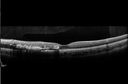

Choroidal Hemangioma - Diffuse - Enhanced Depth Imaging Spectral Domain OCT Line Scan - Abnormal Eye837 viewsChoroidal Thickness is 697 Microns from Diffuse Choroidal HemangiomaFeb 12, 2014

Choroidal Hemangioma - Diffuse - Enhanced Depth Imaging Spectral Domain OCT Line Scan - Abnormal Eye612 viewsChoroidal Thickness is 697 Microns from Diffuse Choroidal HemangiomaFeb 12, 2014